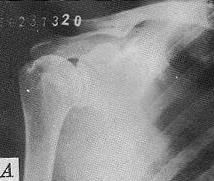

肱骨大結節囊性變

肱骨大結節骨贅形成2、肩關節造影:肩關節造影不作為本病常規檢查方法,主要用於鑑別肩袖是部分更趨加劇,久之使骨結構發生改變。肩峰前下部、肱骨大結節發生硬化、增生或囊性變,肱骨頸上可出現切跡。